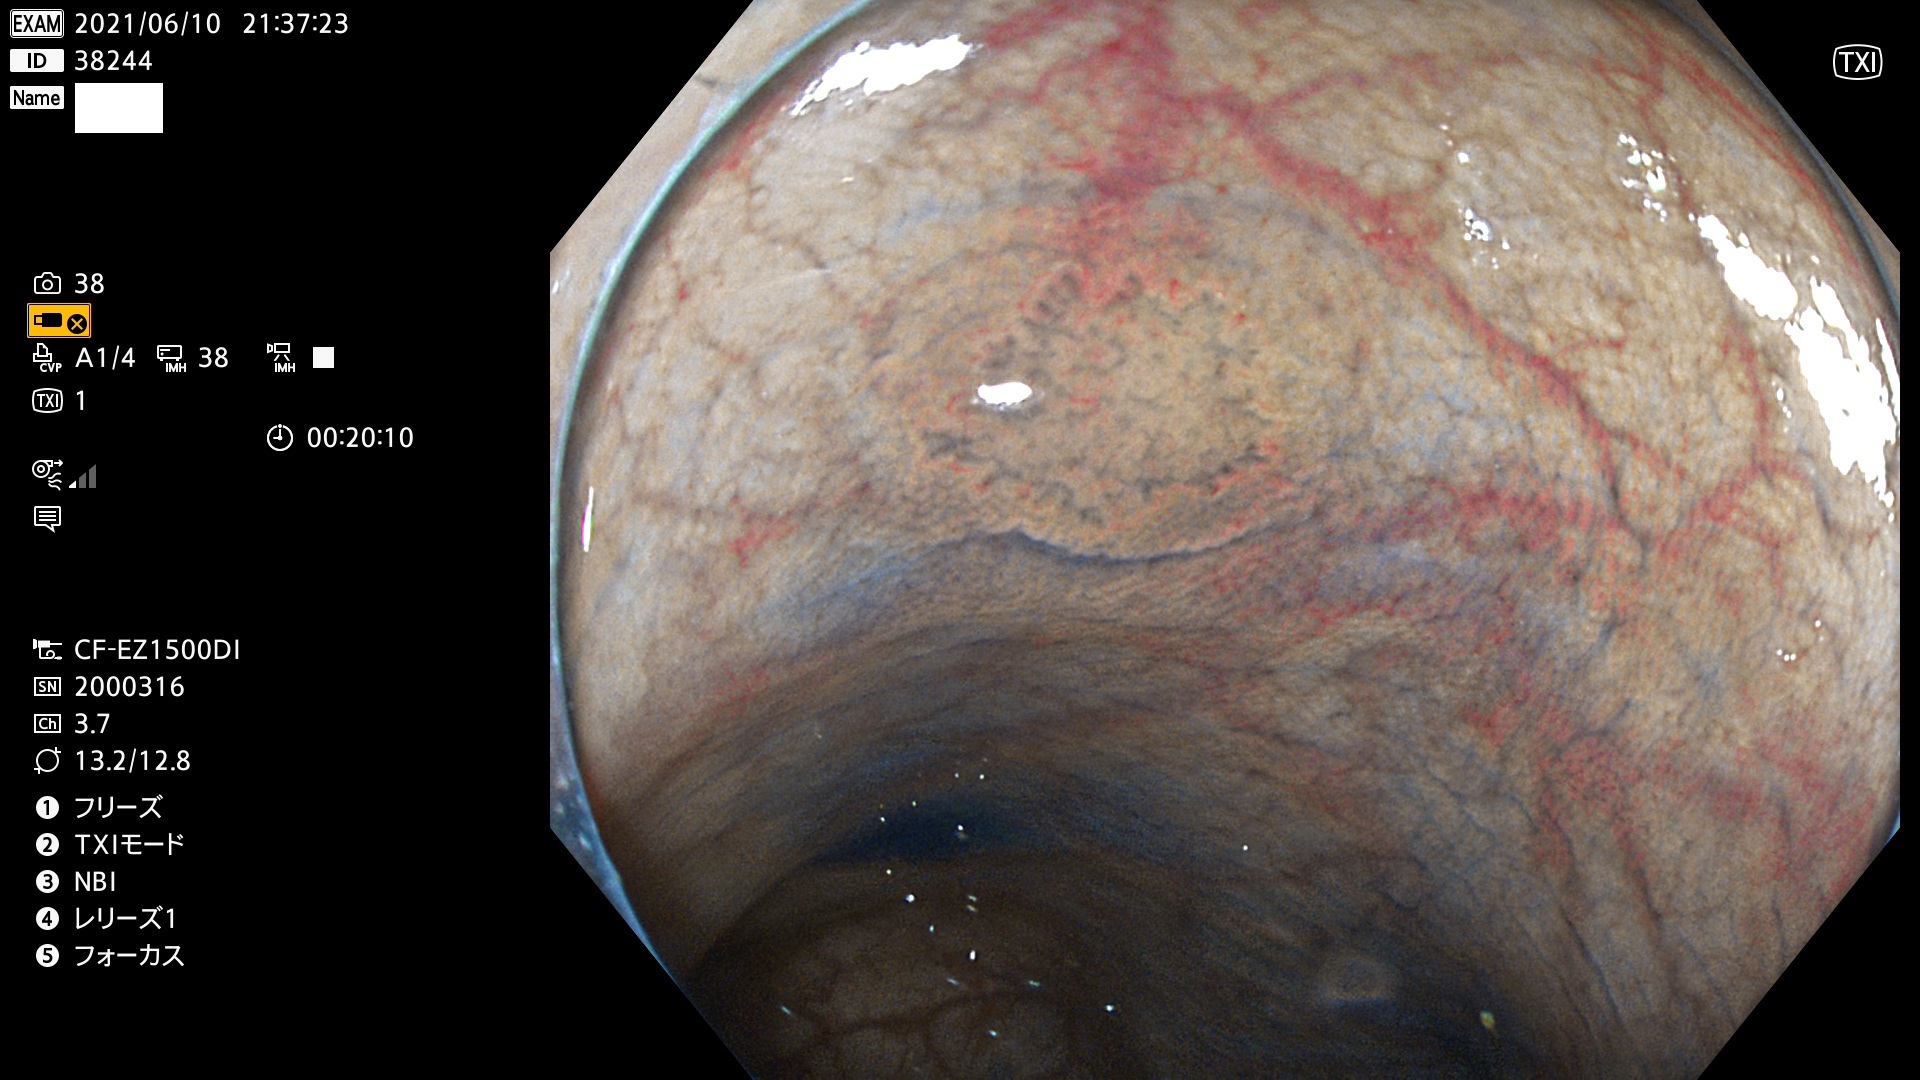

38200 38201 38202 38203 38204 38208 38209 38210 38211 38212 38213 38214 38215 38219 38220(SSAPのみ) 38221 38225 38226 38227 38228 38229 38230 38231 38232(SSAPのみ) 38233 38234 38235 38237 38238 38239 38240 38241 38242 38244 38245 38246 38247 38248 38249 38250 38251 38252 38253 38254 38256 38257 38258 38259 38260(SSAPのみ) 38262 38265 38267 38268(SSAPのみ) 38269 38270 38272 38273 38274 38276 38278 38280 38281 38282 38283 38284 38287 38288 38289 38290 38291 38292 38295 38296 38297 38298 38299(SSAPのみ)

発見困難で危険性の高い平坦型病変(上記100名より抽出)